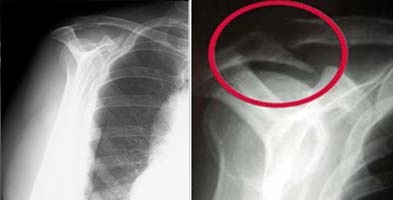

X-rays will often show a "downsloping" acromion which can contribute to the symptoms of impingement syndrome